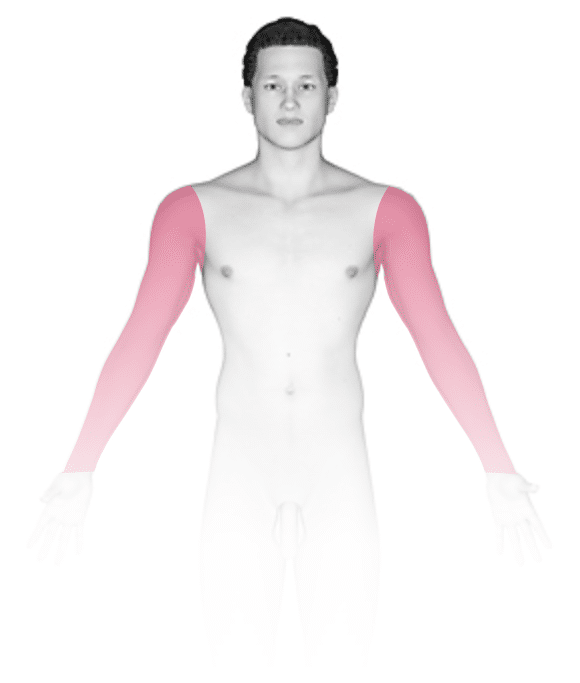

Blisters typically develop on the soles of feet and the palms of hands when there is friction and irritation on the surface layer of the skin.